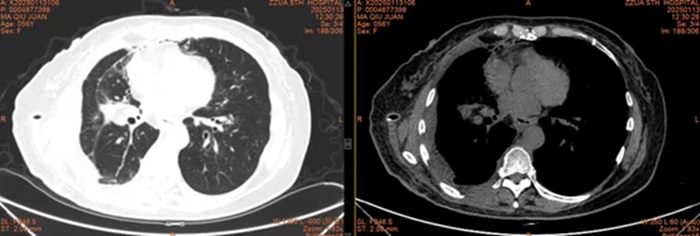

术后CT

患者术后恢复良好,马女士及其家人激动地向高主任表达了深深的谢意。如今,患者现已顺利康复出院,回归正常的生活。